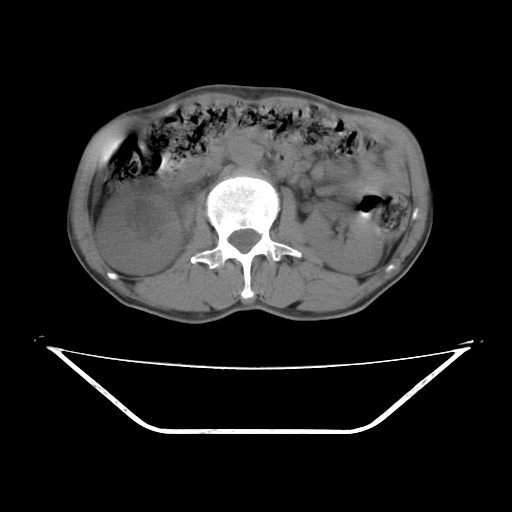

平扫

考虑右肾盂癌,肾动脉受侵,右肾功能减退,右肾盂输尿管积水,管壁增厚,考虑种植转移,应该把下面扫完的

支持右侧肾盂癌伴肾静脉瘤栓形成可能性大,右肾结石.肝右叶后段低密度影,不除外转移.

右肾盂旁ca并肾静脉瘤栓形成/肾功能降低。

右肾结石。

右肾盂癌,肾动脉受侵,右肾盂输尿管积水,管壁增厚,考虑种植转移

支持 右侧肾盂癌伴肾静脉瘤栓形成可能性大,右肾结石;肝右叶后段低密度影,不除外转移。

1.右侧肾盂癌伴肾盂积水。

2.肾脏功能减退,原因有:(1)肾动脉受侵。(2)肾静脉受侵(3)肾积水,等。本例,肾动脉显影较好,但受压明显;肾静脉无明显显示,受压或静脉癌栓,下腔静脉腔内未见明显充盈缺损。

3.右侧上段输尿管扩张,原因:(1)积水所致;(2)种植。